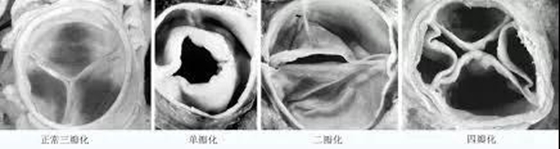

正常的主动脉瓣是由三个等大小的瓣叶构成,此形态被称为“三瓣化”。就主动脉瓣所处的环境和其功能而言,这种等大小的三瓣化是最优结构。人的心脏在胚胎发育过程中会出现少数主动脉瓣非三瓣化的异常情况,如单瓣化、二瓣化、四瓣化,主动脉瓣结构的异常带来的结果有两个:一是主动脉瓣功能的异常,即指瓣口狭窄或者关闭不全;二是不良的血液流场,湍流或者涡流会使主动脉瓣瓣叶受损,过早出现瓣叶脱垂、钙化或发生感染。